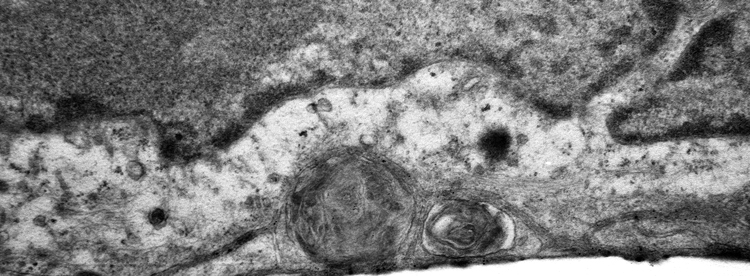

Electron microscopy (top) and confocal microscopy (below) analyses of patient-derived SFD hiPSC-RPE demonstrate presence of sub-RPE drusen-like deposits (the central hallmark of SFD and similar maculopathies) that contain major constituents of drusen in the human eye including APOE (shown in red in the confocal image). Galloway et al PNAS 2017